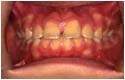

乱食い歯

治療前 乱食い歯 受け口 開口

治療後 乱食い歯 受け口 開口